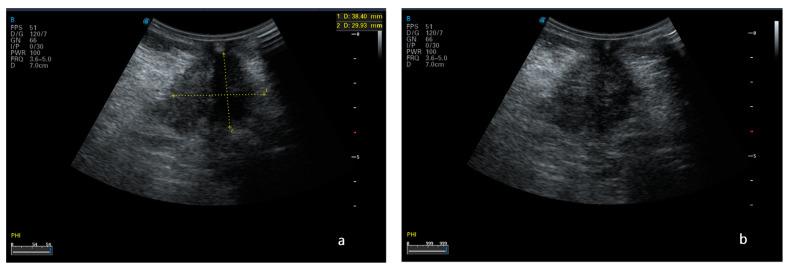

Peritoneal carcinosis is a condition characterized by the spread of cancer cells to the peritoneum, which is the thin membrane that lines the abdominal cavity. It is a serious condition that can result from many different types of cancer, including ovarian, colon, stomach, pancreatic, and appendix cancer. The diagnosis and quantification of lesions in peritoneal carcinosis are critical in the management of patients with the condition, and imaging plays a central role in this process. Radiologists play a vital role in the multidisciplinary management of patients with peritoneal carcinosis. They need to have a thorough understanding of the pathophysiology of the condition, the underlying neoplasms, and the typical imaging findings. In addition, they need to be aware of the differential diagnoses and the advantages and disadvantages of the various imaging methods available. Imaging plays a central role in the diagnosis and quantification of lesions, and radiologists play a critical role in this process. Ultrasound, computed tomography, magnetic resonance, and PET/CT scans are used to diagnose peritoneal carcinosis. Each imaging procedure has advantages and disadvantages, and particular imaging techniques are recommended based on patient conditions. Our aim is to provide knowledge to radiologists regarding appropriate techniques, imaging findings, differential diagnoses, and treatment options. With the advent of AI in oncology, the future of precision medicine appears promising, and the interconnection between structured reporting and AI is likely to improve diagnostic accuracy and treatment outcomes for patients with peritoneal carcinosis.

腹膜癌是一种以癌细胞扩散至腹膜为特征的病症,腹膜是衬于腹腔的一层薄膜。它是一种严重的病症,可由多种不同类型的癌症引发,包括卵巢癌、结肠癌、胃癌、胰腺癌和阑尾癌。腹膜癌中病变的诊断和定量对于该病症患者的管理至关重要,而影像学在这一过程中发挥着核心作用。放射科医生在腹膜癌患者的多学科管理中起着至关重要的作用。他们需要对该病症的病理生理学、潜在肿瘤以及典型的影像学表现有透彻的了解。此外,他们需要知晓鉴别诊断以及各种可用影像学方法的优缺点。影像学在病变的诊断和定量中起着核心作用,放射科医生在这一过程中起着关键作用。超声、计算机断层扫描、磁共振成像和正电子发射断层显像/计算机断层扫描(PET/CT)用于诊断腹膜癌。每种成像检查都有其优缺点,会根据患者情况推荐特定的成像技术。我们的目的是向放射科医生提供有关合适技术、影像学表现、鉴别诊断和治疗方案的知识。随着人工智能在肿瘤学中的出现,精准医学的未来似乎很有前景,结构化报告与人工智能之间的相互联系可能会提高腹膜癌患者的诊断准确性和治疗效果。